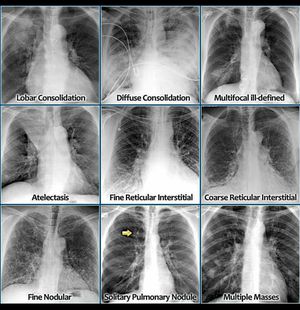

Chest X-Ray

Lung disease

Cxray

Atelectasis

Consolidation

Lungs consolidation content and pattern

Acute and chronic consolidation